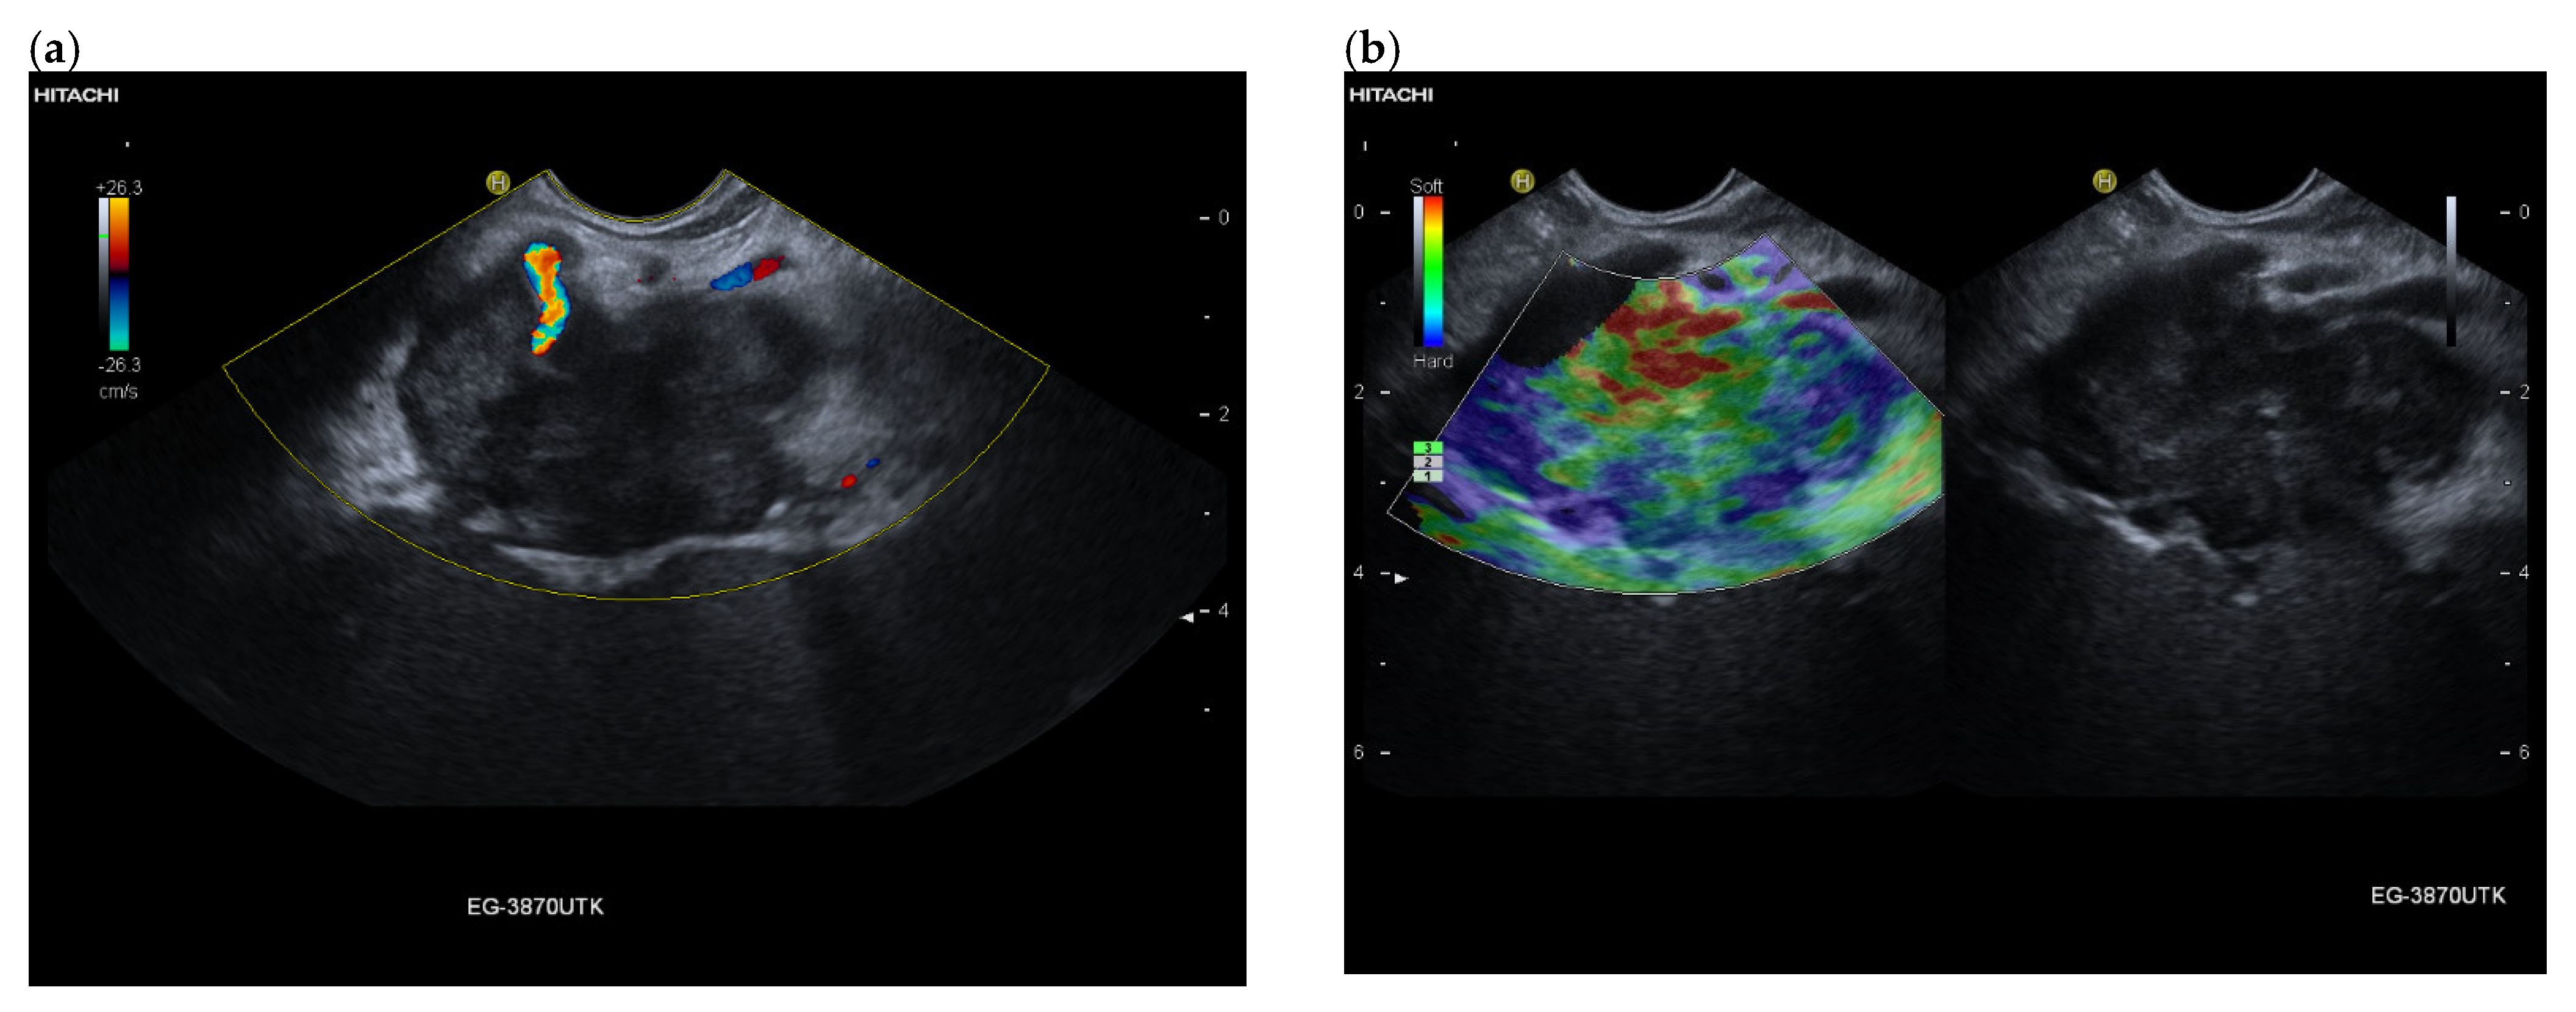

3.4. CEUS and CH-EUS

B-mode US/EUS

| Mostly hypoechoic, homogeneous, or heterogeneous More likely well-defined borders (46%) Anechoic and hyperechoic lesions are possible | Hypoechoic, typically heterogeneous, irregular borders | Hypoechoic, mostly homogeneous, smoothly bordered. Cystic components or cystic solid PanNENs are possible |

| Mostly no infiltration into adjacent vessels | Infiltration around and into the vessels | No infiltration into adjacent vessels |

| Colour Doppler Imaging | RCC metastases are hypervascularized Most other pancreatic metastases are hypovascularized | No hypervascularization | Hypervascularized |

| Elastography (small lesions up to 15 mm) [67] | 41% softer or isoelastic, 59% stiffer compared to pancreatic parenchyma | 4% soft or isoelastic, 96% stiffer compared to pancreatic parenchyma | 64% soft or isoelastic, 36% stiffer compared to pancreatic parenchyma |